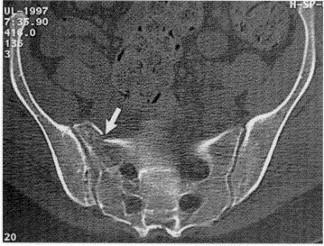

• CT

• diagnostic study of choice

• recommend coronal and sagittal reconstruction views

• Denis classification

• zone 1

• fracture lateral to foramina

• most common (50%)

• nerve injury rare (5%)

• usually occurs to L5 nerve root

• zone 2

• fracture through foramina

• zone 3

• fracture medial to foramina into the spinal canal

• highest rate of neurologic deficit (60%)